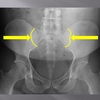

posterior arch of C1

How well did you know this?

1

Not at all

2

3

4

5

Perfectly

10

Q

A

lamina c2-c7